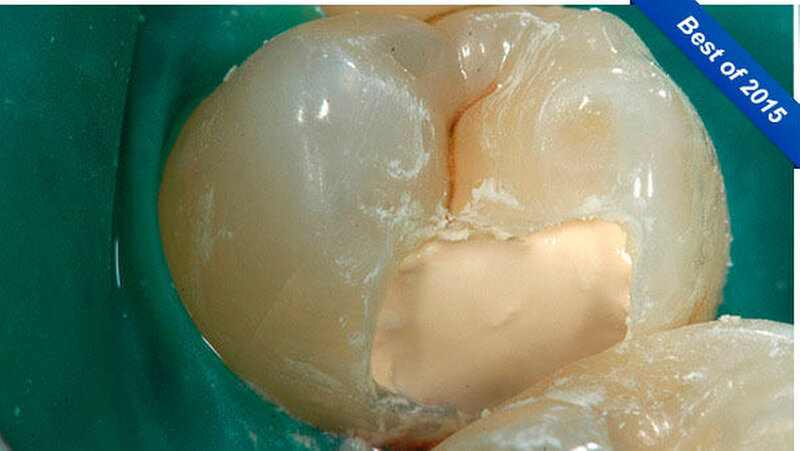

-Schnee positiv und in der Perkussionsprobe negativ. Nach ausführlicher Beratung des Patienten und Aufklärung über den Therapieablauf wurde eine terminale Infiltrationsanästhesie (Septanest, Septodont, Niederkassel) an Zahn 14 durchgeführt und Kofferdam gelegt (Abbildung 3). Nach Primärpräparation (Abbildung 4) kam es bei der vollständigen Exkavation der Dentinkaries zu einer iatrogenen Freilegung der Pulpa (Abbildung 5).

Klinisch stellte sich das Pulpagewebe als vital und ohne ausgeprägte Blutung dar, so dass zum Erhalt der Pulpavitalität eine direkte Überkappung in Betracht gezogen werden konnte. Zur Blutstillung sowie zur Reinigung und Desinfektion der Kavität wurde eine Kavitätentoilette mit NaOCl (2,5 Prozent) durchgeführt. Biodentine (Septodont, Niederkassel) wurde als Mittel für die direkte Überkappung ausgewählt. Der Zement wurde nach Herstellerangaben angemischt und sowohl auf das freiliegende Pulpagewebe als auch auf das Dentin im Sinne einer Unterfüllung appliziert (Abbildung 6).

Nach dem Anmischen benötigt das Material etwa 15 Minuten für die initiale Abbindung. Während dieser Abbindezeit änderte sich das Aussehen der Zementoberfläche von feucht-glänzend (Abbildung 6) hin zu matt (Abbildung 7). Dieser Zeitraum muss abgewartet werden, ehe man die Füllungstherapie fortsetzen kann. Während der Wartezeit erfolgte das Legen einer Matrize (Composi-Tight 3D; Garrison, Übach-Palenberg) und eines Keils (Abbildung 8).